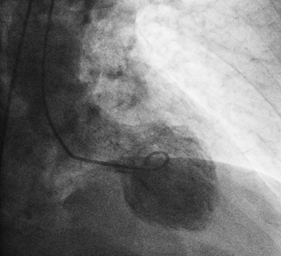

A 81year old gentleman presented to the emergency department accompanied by emergency physician and paramedics with typical angina symptoms for last 1hour associated with Dyspnoe, nausea  and vomitimg. The chest pain has subsided with administration of Morphin i.v. On arrival in the emergency department, one immediate 12-lead ECG  was done, that showed lateral wall  ST-elevated myocardial infarction (Figure 1). Wihout delay as per the current guidelines one emergency  angiogram was done, that revealed one occluded Ramus diagonalis branch of Left anterior descending artery(Figure-2) and one Plaque rupture in mid segment of right coronary artery with subtotal occlusion (Figures 2 & 3). Immidiately the coronary flow in Ramus diagonalis -2 was regained and the culprit lesion was treated with 2 drug eluting stents  2,25X14mm size, the end result was TIMI III Flow in Ramus diagonalis -2. During the procedure the EKG showed ST elevation in lead II, III and aVF with intermittent Atrioventricular Block III, Blood pressure was 100/56mm Hg and heart rate was 65 per minute. We decided to perform the angioplasty of Right coronary artery. The flow in right coronary artery was restored and the culprit lesion as treated with 2 Drug eluting stents 3.0X19 mm and 3,5X 14mm, resulting in TIMI III Flow. The ST elevation leads II, III and aVF were settled.

Figure 2 Coronaryangiography.

Figure 3 Coronaryangiography.